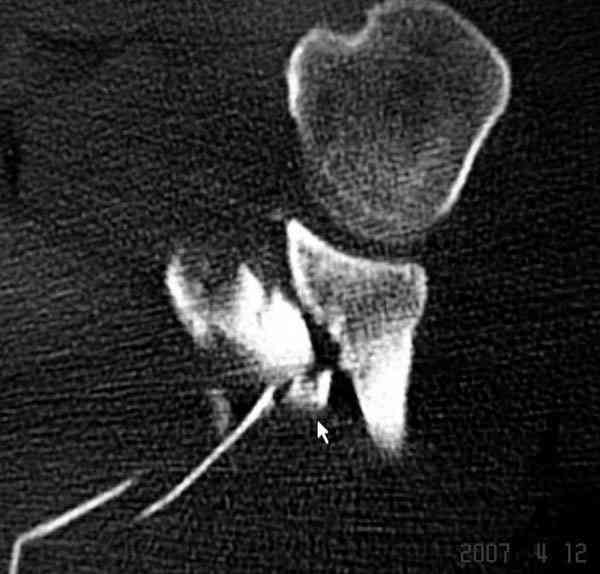

К-томографические и Трехмерные(3D)снимки крайне важны для определения внутрисуставных переломов и классификации.

Кроме анатомической классификации, переломы лопатки делятся на стабильные и нестабильные, внутри- и внесуставные и с вовлечением суставной поверхности.

Также показания к оперативному вмещательству на лопатке появляются, когда смещения суставной поверхности медиально 9 и более мм и при угловом смещении суставной поверхности 40 и более градусов.

В 1993 Goss описал верхне плечевой поддерживающий комплекс (SSSC-superior shoulder suspensory complex), костно-связочное кольцо из акромиона, коракоида, ключицы и гленоида. Повреждения двух или более элементов из перечисленных доказывают наличие флотирования, и рекомендуется операция.